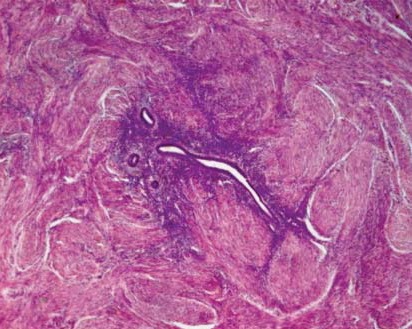

Результаты и их обсуждение. Гистологически установлено, что одной из морфологических особенностей Ам, независимо от глубины расположения эндометриоидных очагов в толще миометрия, является постоянство перифокальной лейомиоматозной гиперплазии (ПЛГ) – гладкомышечная пролиферация вокруг эндометриоидных гетеротопий. Она была обнаружена у всех пациенток 2-й группы и в 93,9% случаев у больных 1-й группы. Перифокальные лейомиоматозные пролифераты вместе с ЭГ формировали единые тканевые комплексы, которые топографически были четко отграничены от окружающего их миометрия (рис. 1).

Рис. 1. Очаг Ам с ПЛГ, отграниченный от окружающего миометрия. Окраска – гематоксилин-эозин, ув. х200